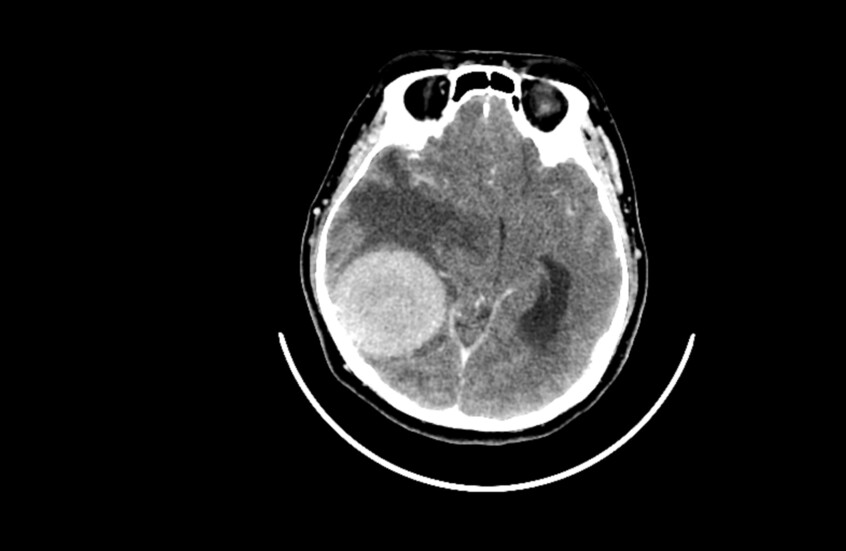

دراسة صادمة.. القلق والدوار يرتبطان بأورام الدماغ!

توصلت دراسة حديثة إلى وجود علاقة بين القلق والدوخة من جهة، والأورام الدماغية الحميدة من جهة أخرى.

ويرتبط الورم الشفاني الدهليزي، أو كما يعرف أيضا باسم ورم العصب السمعي (وهو ورم حميد يصيب العصب المسؤول عن السمع والتوازن وينمو ببطء)، عادة بأعراض مثل فقدان السمع والطنين والدوار. لكن الدراسة الجديدة تكشف أن للعوامل النفسية دورا محوريا في شدة هذه الأعراض.